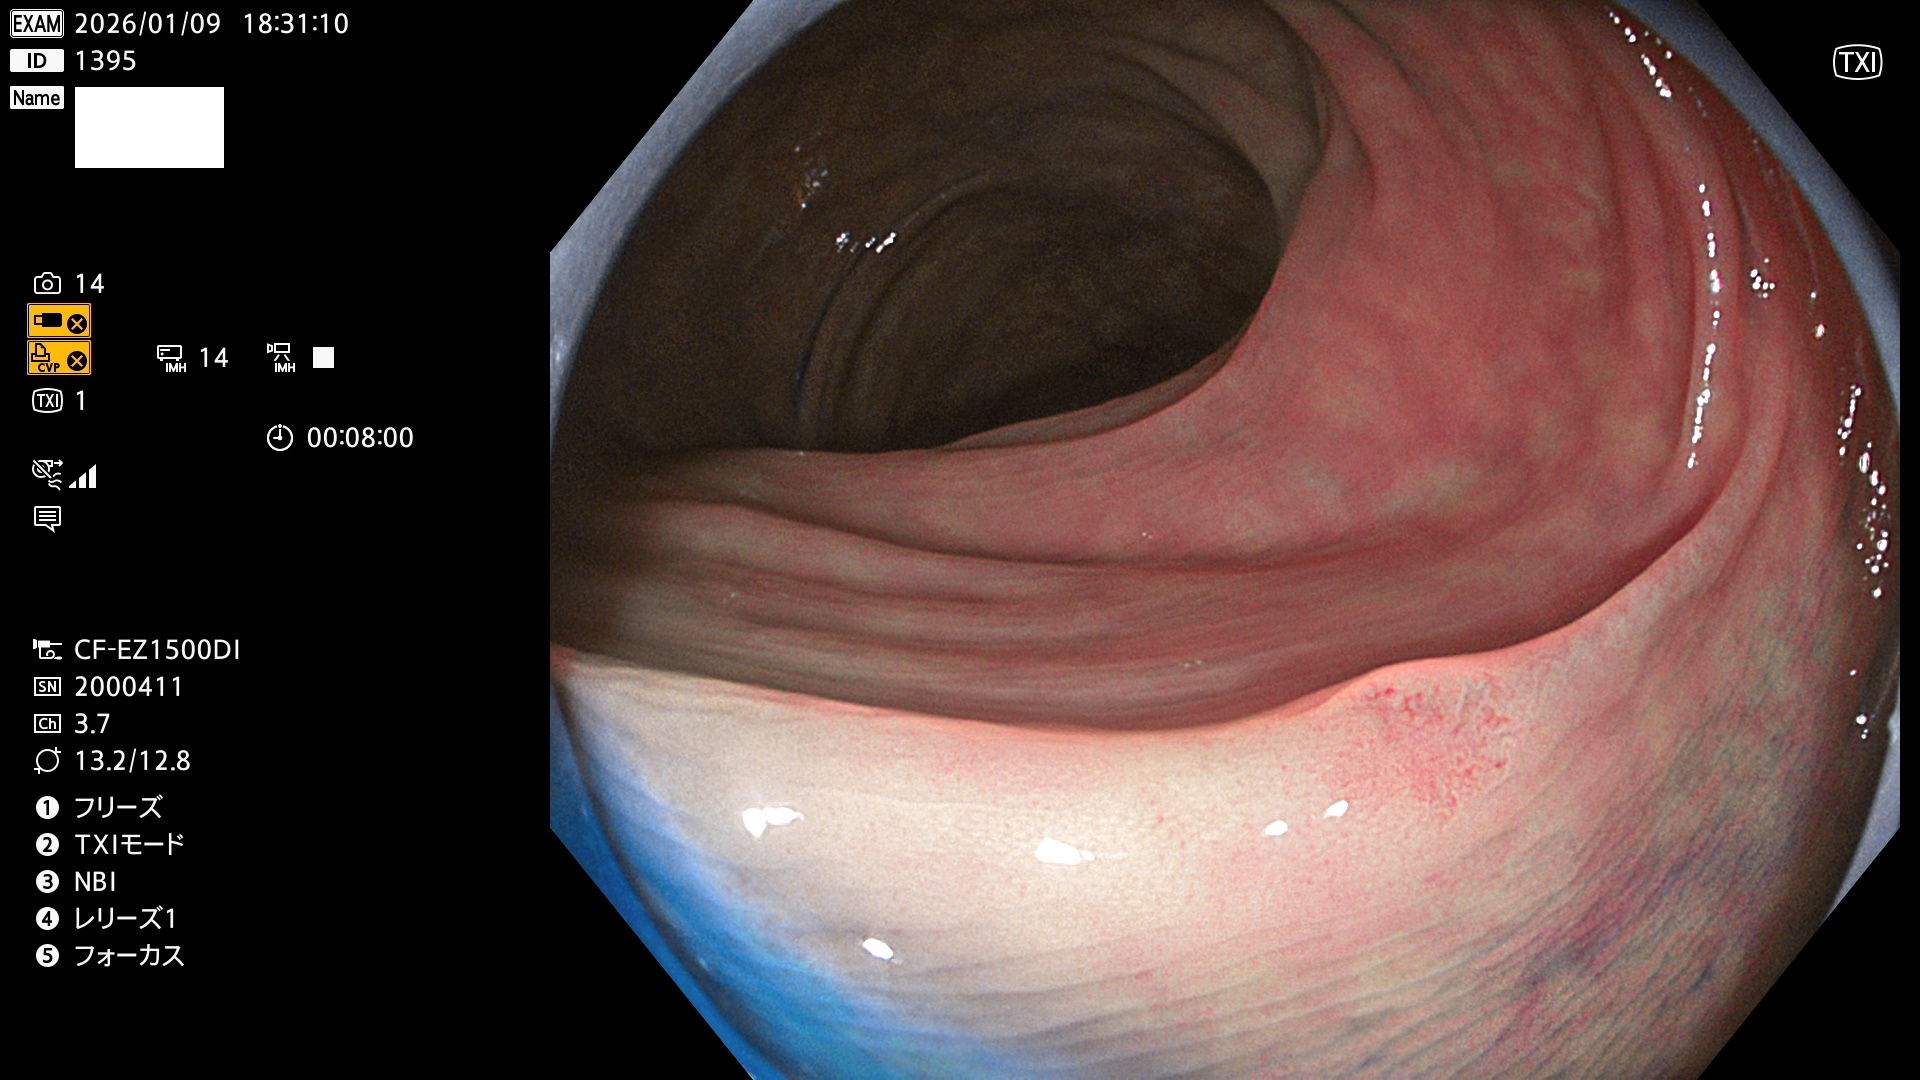

完全に平坦な物をUb、陥凹している物をUcと呼びます。Ubは認識が困難で、Ucはびらん(炎症)と紛らわしいために見落とされやすく、「内視鏡後・大腸癌」の原因になります。

毎週の検査(木・金・土・日)に発見されたUbとUc型・腺腫を、その週の日曜の夜にUPし1週間、提示します。

写真公開の目的は「透明性・信憑性の担保」ですが、公開を希望されない方はメールで御連絡下さい。直ちに削除いたします。

2026年1月8日〜1月11日の4日間(40件)6個 (Uc_ADR=6個/40人=15%)